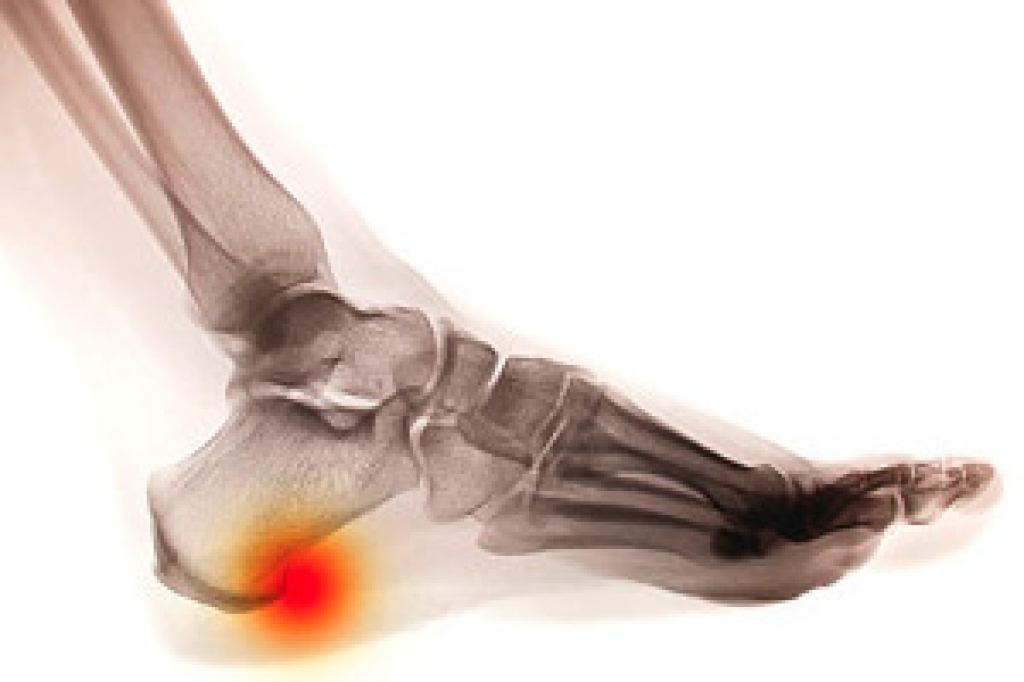

Calcaneal spurs, also known as heel spurs, are bony protrusions that form on the underside of the heel bone, which is the calcaneus. These spurs develop in response to long-term inflammation and tension on the plantar fascia, a band of tissue that connects the heel bone to the toes. The repetitive stress and strain can lead to the formation of calcium deposits, resulting in the development of bony growth. Individuals with calcaneal spurs often experience symptoms such as sharp pain in the heel, particularly during weight-bearing activities like walking or standing. The pain may intensify with the first steps in the morning or after prolonged periods of rest. Additionally, tenderness and swelling around the affected area are common. While some people with calcaneal spurs may not experience any symptoms, others may find the pain debilitating, impacting their daily activities. If you have heel pain, it is strongly suggested that you visit a podiatrist who can accurately diagnose and treat heel spurs.

Heel spurs are formed by calcium deposits on the back of the foot where the heel is. This can also be caused by small fragments of bone breaking off one section of the foot, attaching onto the back of the foot. Heel spurs can also be bone growth on the back of the foot and may grow in the direction of the arch of the foot.

The pain associated with spurs is often because of weight placed on the feet. When someone is walking, their entire weight is concentrated on the feet. Bone spurs then have the tendency to affect other bones and tissues around the foot. As the pain continues, the feet will become tender and sensitive over time.